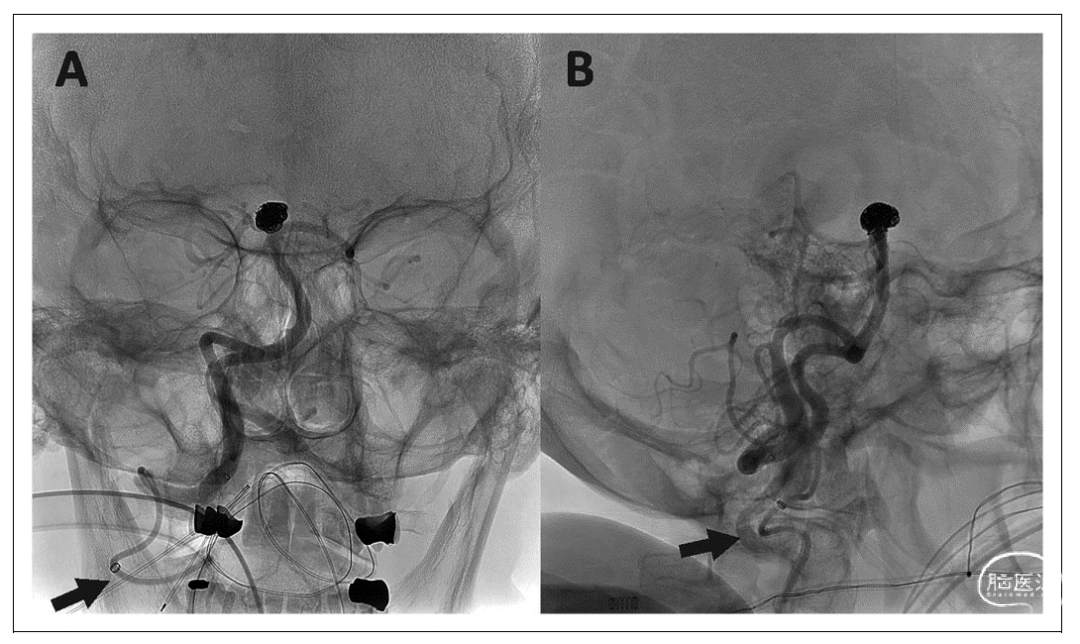

在另一例中,由于出现桡动脉环并伴有血管痉挛,我们不得不通过尺动脉入路。桡动脉入路为各种微导管提供了良好的稳定性,允许进行各种各样的手术,包括颅内动脉瘤治疗(图4)、卒中、硬脑膜动静脉瘘及MMA栓塞术。

图4:右侧椎动脉AP位(A)和侧位(B)血管造影显示BMX81导引导管导航到右侧椎动脉V3段(黑色箭头),为基底动脉尖动脉瘤栓塞提供支撑。